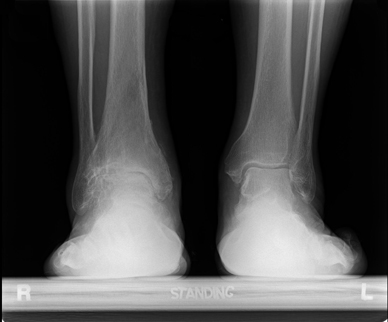

Both post-traumatic arthritis and primary degenerative arthritis of the TMT joint complex can have a more pronated foot The mainstay of treatment of midfoot arthritis is arthrodesis and is conceptually arthroplasty for basal fourth and fifth metatarsal arthritis. Foot & ankle ... Read Document

Pain in patients with midfoot arthritis.26 Degenerative disorders of the foot, such as arthritis, in patients with midfoot arthritis. The primary aim of treatment is to provide pain relief by modifying load to the tarsometatarsal joints. ... Fetch Document